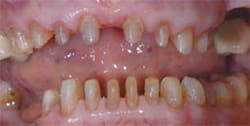

A 74-year-old woman presented to the Department of International Advanced Esthetic Dentistry Program at New York University College of Dentistry. Her chief complaint was the appearance of her teeth. She believed they were old, thin, dark, small, and spaced (Figure 1). She wanted her teeth to be whiter but natural and “normal” size without spaces. She reported no pain symptoms related to the TMJs, musculature, or other dental structures. Noticeable wear was present on the maxillary and mandibular anterior teeth and the remaining posterior natural teeth (Figure 2 and Figure 3). Vertical dimension was closed slightly, and centric occlusion and centric relation were coincidental. Ideally, all the posterior teeth would be restored and the vertical dimension increased in the posterior about 1 mm. This would result in a 3-mm anterior correction. However, financial constraints prohibited this.

Radiographs, photographs, and diagnostic casts were obtained. The findings from an esthetic analysis revealed a straight profile, upper and lower midline deviation to the right, moderate overjet, and normal occlusion. Gingival papillae were blunted, and the gingival zenith was irregular (Figure 4). The maxillary anterior teeth did not touch the lower lip. Also, the patient had a high smile line with 2 mm to 3 mm of display; the midline was off to the right of the philtrum; no teeth showed in repose; the buccal corridor was normal; a full smile exposed 12 teeth; and she had a reverse smile line. The recent dental history included extractions of teeth Nos. 29 and 31 to treat nonrestorable decay under a fixed bridge, endodontic treatment for tooth No. 13, a sinus lift using Bio-Oss® (Osteohealth, https://www.osteohealth.com) mixed with autogenous bone, and two implant placements in the upper left quadrant for teeth Nos. 14 and 15.

Figure 3 Occlusal view of the mandibular arch demonstrating edentulous area and worn posterior teeth. | Figure 4 Patient presented with blunted gingival papilla, irregular gingival zenith, reverse smile, and an extruded right posterior segment. | ||||||